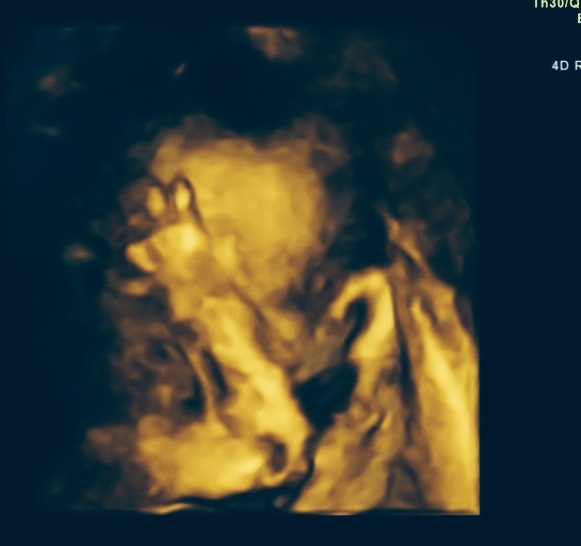

my dad calls him a fighter because of his fists up like that lol

This one is pretty cute. Looks like he is smiling